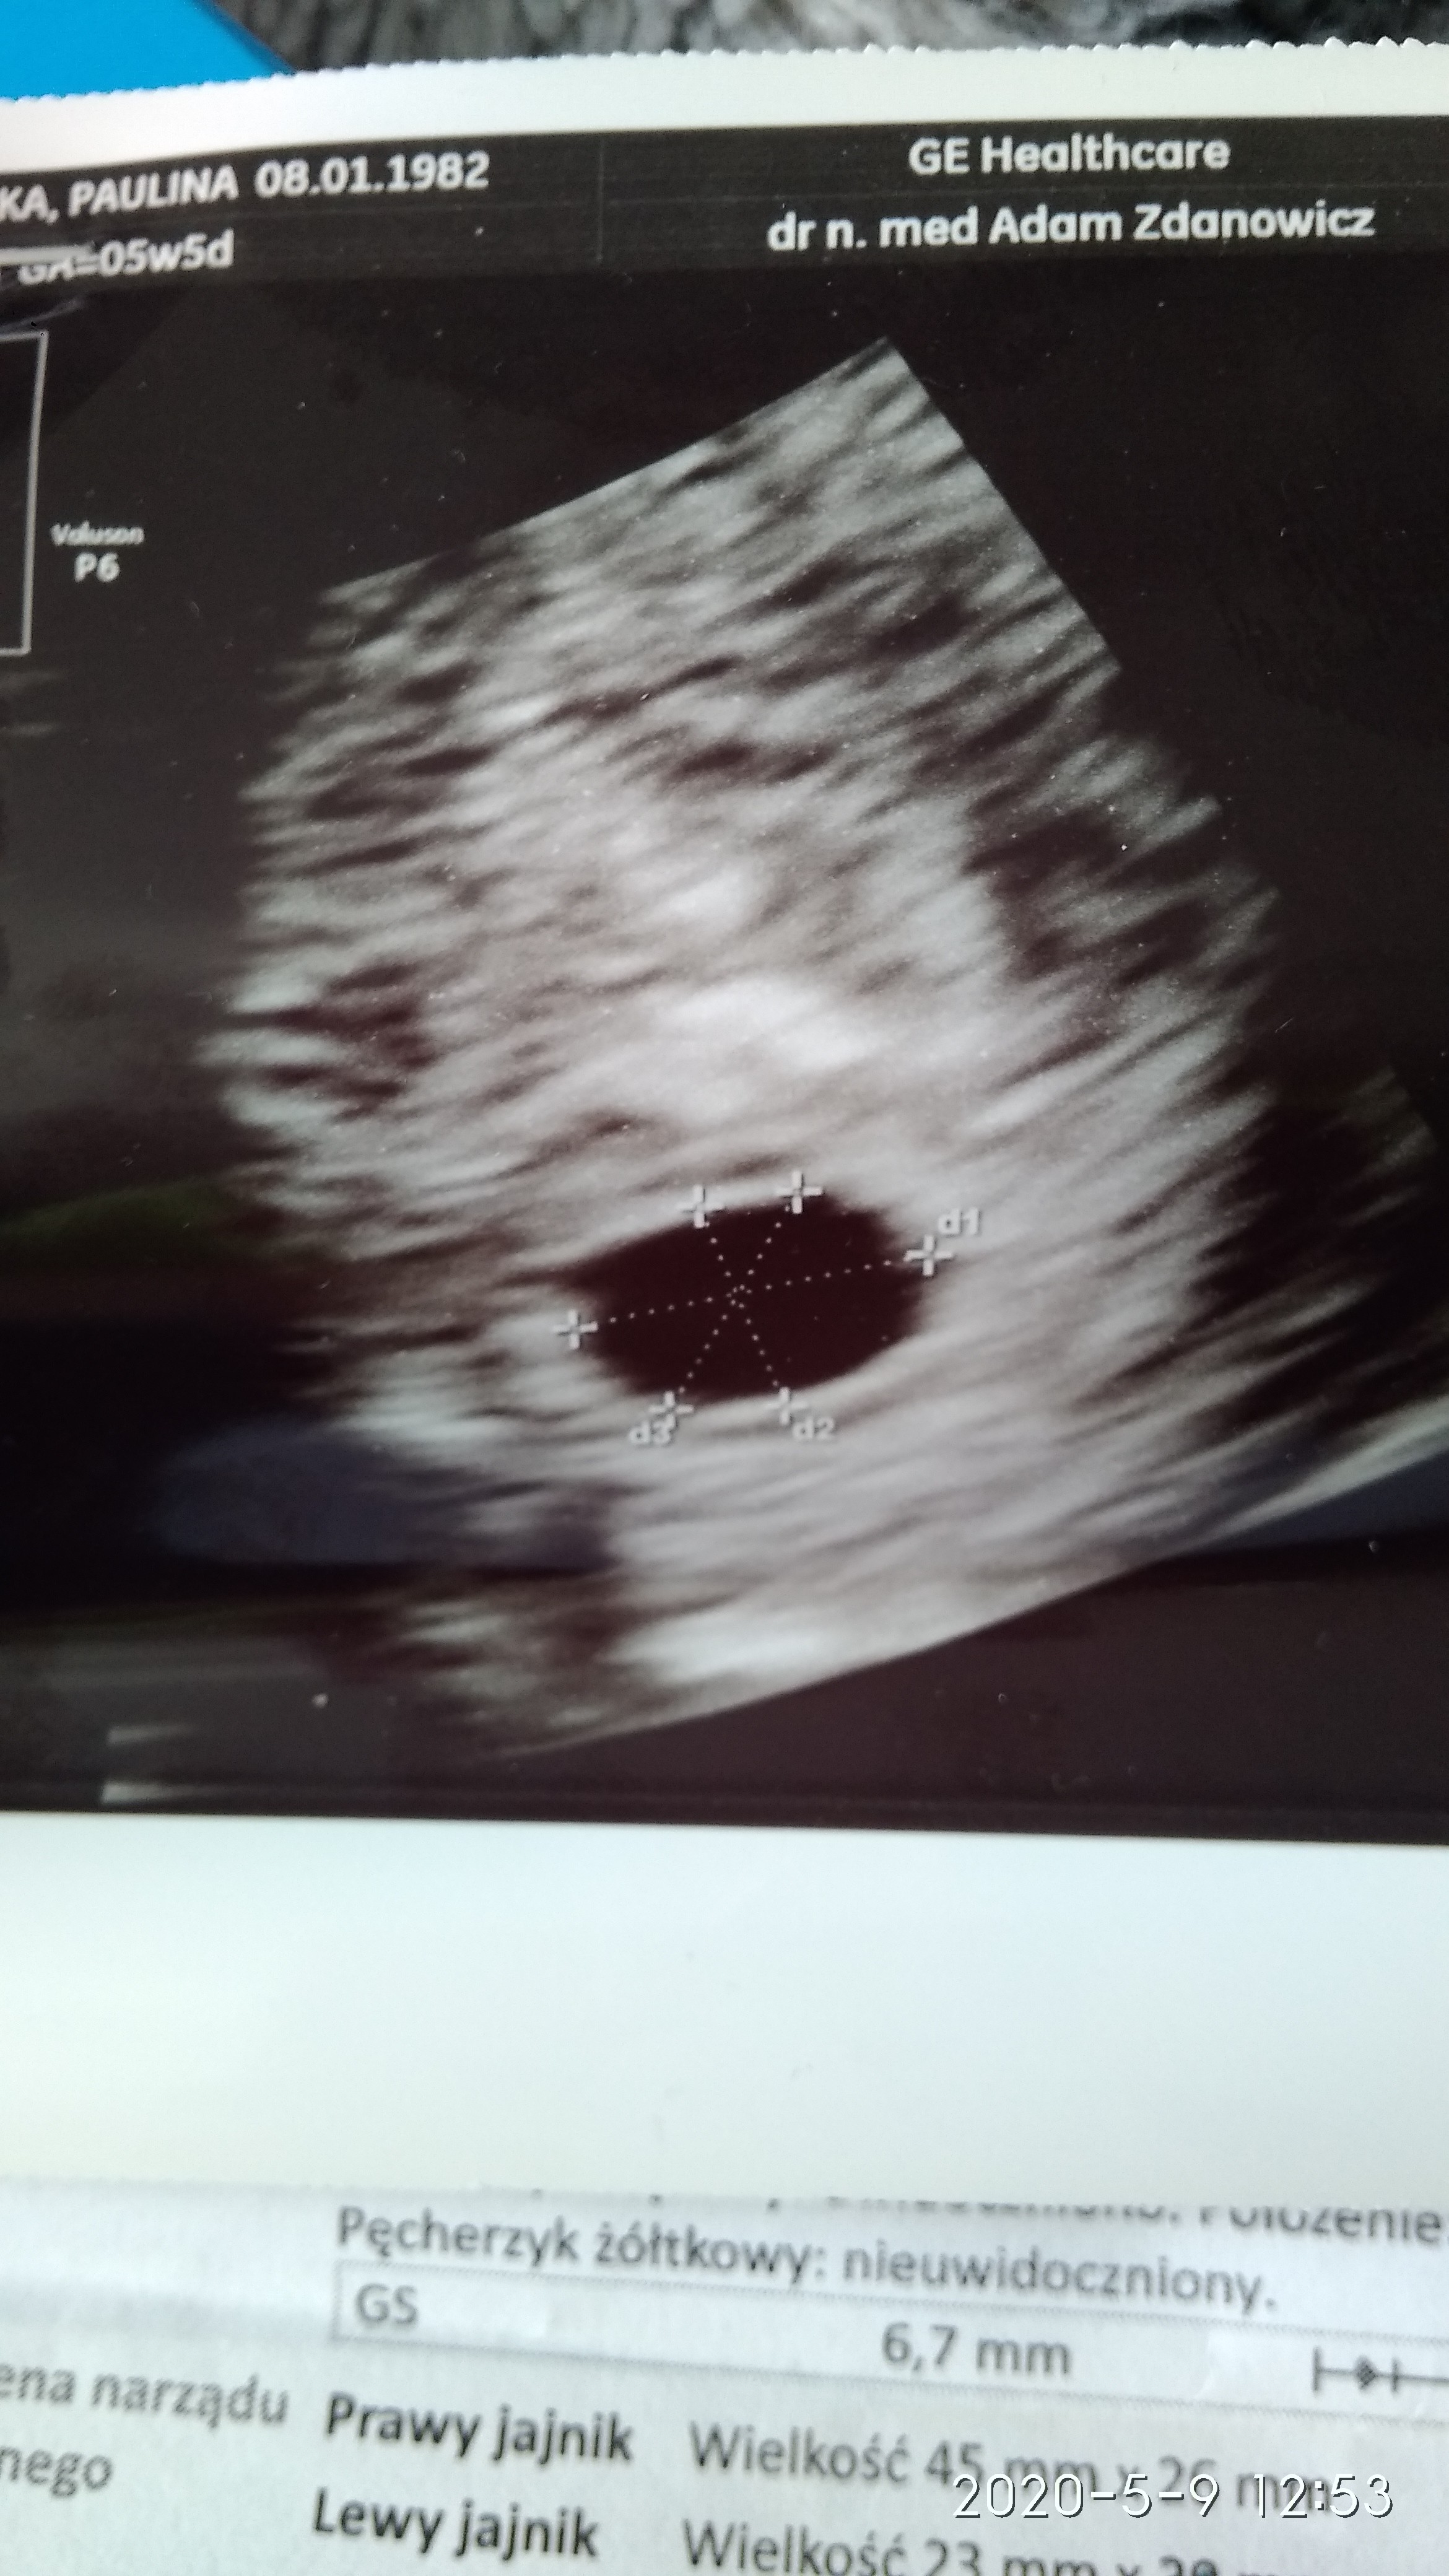

Byłam dzisiaj na przyspieszonej wizycie , dostałam letrox na zbicie TSH a przy okazji USG i mam i ja swojego kropka😀

Załączniki